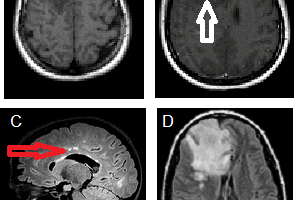

ADEM

ADEM (acute disseminated encephalomyelitis) is an autoimmune demyelinating disorder distinct from multiple sclerosis or Devic’s disease. Read more »